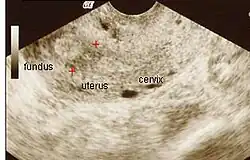

Síndrome de Asherman (AS), também chamada de sinéquias uterinas ou adesões intrauterinas, é a condição caracterizada pela presença de adesões e/ou fibrose no interior da cavidade uterina devido a cicatrizes.